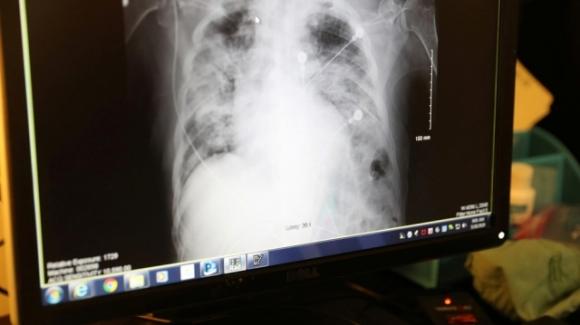

Hình ảnh chụp X-quang phổi của bệnh nhân COVID-19. Ảnh: Reuters